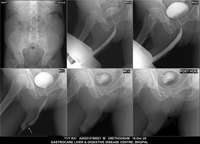

Section: URETHROGRAM Total: 95 images

BaM Enteroclysis Loopogram BaE Fistulogram Urethrogram HSG